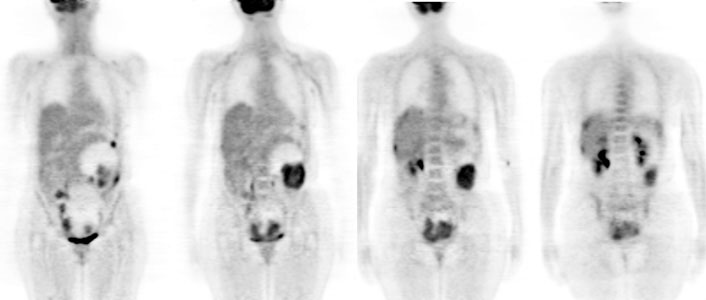

PET > PET tumor imaging > Ovary